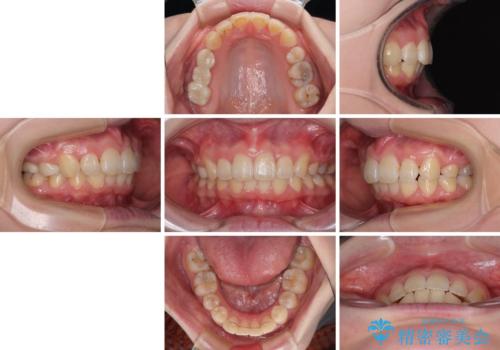

矯正治療後には、上顎欠損部をオールセラミックブリッジにて補綴治療を行うこととしました。

予想通りに治療は困難を極め、その上途中来院されない時期があったため、非常に長期間に及びましたが、周囲の方々が驚愕するほど口元の印象を改善することができました。